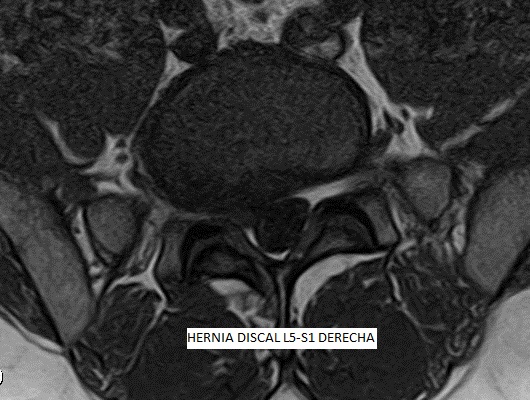

Les patologies del disc intervertebral es consideren de significativa contribució a la sensació dolorosa. Les hèrnies discals, protusions discals i l'artrosi, són les patologies degeneratives més comuns. La causa més freqüent de la Lumbàlgia o Dolor Lumbar és la degenerativa, associada a canvis biomecànics a la columna vertebral, resultant en un dany que pot arribar a severa intensitat i provocar una gran limitació de la nostra qualitat de vida.